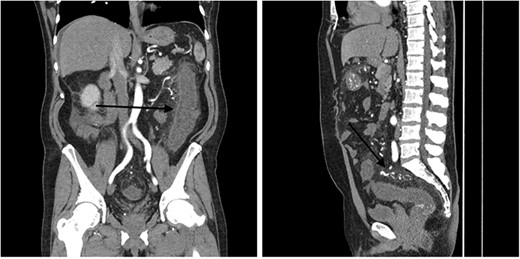

A 51-year-old male patient presented to the emergency department with 24 hours of severe abdominal pain and rectal bleeding, as well as 4 months history of non-mucous diarrhoea with stool frequency of up to 12 episodes per day. He had a background of poorly differentiated adenocarcinoma of the ascending colon (T3N0M0), which was treated with laparoscopic right hemicolectomy 1 year prior to this presentation. His follow-up colonoscopy 6 months prior to admission demonstrated evidence of diverticular disease and colitis although biopsies were normal. On admission, the patient was haemodynamically stable and physical examination did not reveal signs of peritonism. Laboratory studies demonstrated a haemoglobin drop of 4 g/dl (15.9–10.8 g/dl) but no evidence of abnormal coagulation. Stool samples were negative for infectious causes. The diagnosis of ischaemic colitis was made by contrast-enhanced computed tomography (CT) scan with CT angiography, which revealed AVMs in the territory of SMA and IMA and acute massive congestive ischaemic colitis affecting remaining colon and rectum (Figs 1 and 2).

Contrast-enhanced abdominal CT images of inferior mesenteric AVM causing acute congestive ischaemic colitis affecting descending and sigmoid colon, and rectum.